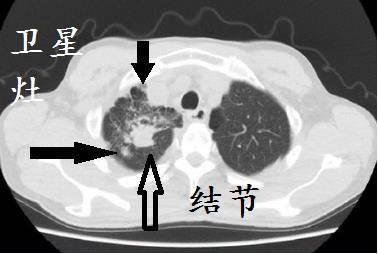

这样读片才正确:转移性肺癌 ct 表现特点大盘点_尘肺

一文掌握 6 种胸部 ct 常见征象